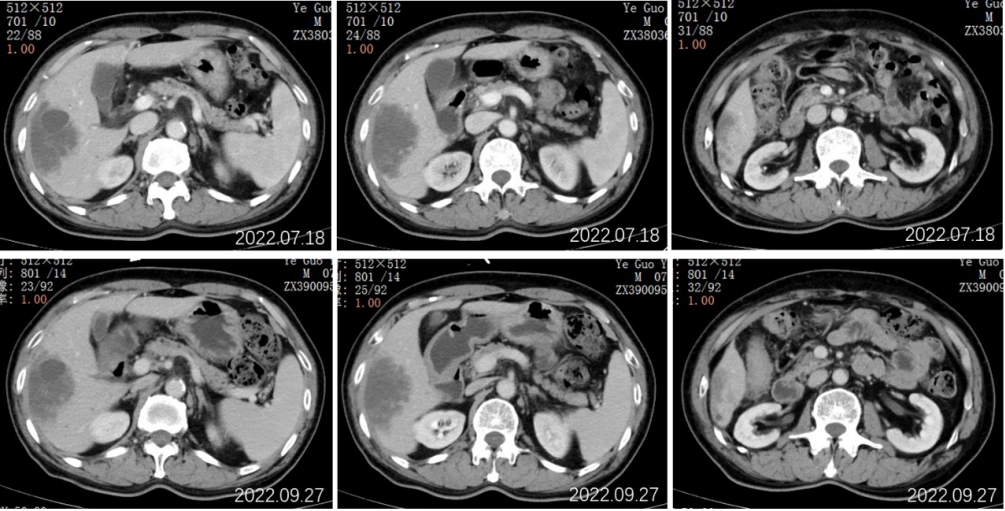

2022.09.27胸部CT平扫:1.两肺多发小结节、类结节影,较前相似,转移性考虑;2.两侧胸腔少量积液较前已吸收。3.左侧第5后肋骨质破坏。

2022.09.27腹部CT增强:肝胆管细胞癌治疗后复查:1、肝右叶多发占位,较前大小相仿,目前仍可见活性;2、肝内及双肾多发小囊肿,相仿;肝S2段小血管瘤考虑,相仿;3、慢性胆囊炎改变;4、肝内钙化灶;前列腺钙化灶。

2022.07.19行全腹部平扫+增强:肝右叶可见一类圆形稍低密度影,累及肝S5-8段,边界欠清,约80mm*50mm*98mm大小,密度欠均匀,增强动脉期病灶边缘轻度强化,门脉期边缘环状强化更为明显,中心见无强化坏死区,病灶周围S6段另见数个小结节样类似强化灶;肝内另见数个类圆形低密度灶,径约7-25mm,增强扫描未见强化。

结论:1、肝右叶多发占位,倾向恶性肿瘤,考虑①胆管细胞癌;②转移瘤不除外;2、肝内及双肾多发小囊肿;3、慢性胆囊壁炎改变;4、肝内钙化灶;前列腺钙化灶。